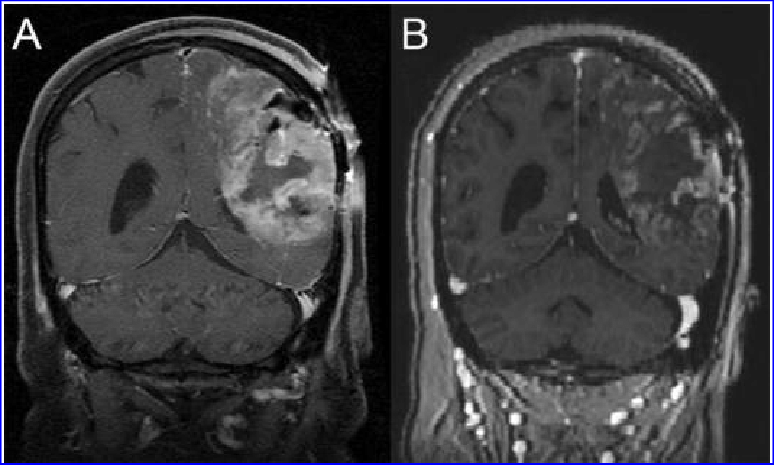

胶质母细胞瘤接受G207治疗前后对比。(A)治疗前(B)G207的接种后一个月,表明对G207有明确的反应。

这项试验纳入了12例7至18岁的高级神经胶质瘤患者,都是经过标准治疗后进展的晚期患者。接受G207病毒注射后,一些患者还接受单次小剂量辐射,来增强病毒复制并在整个肿瘤中扩散。 结果显示,在11例患者中观察到了响应,中位总生存期为12.2个月,比进行性儿童高级神经胶质瘤的典型总生存期增加了120% 。